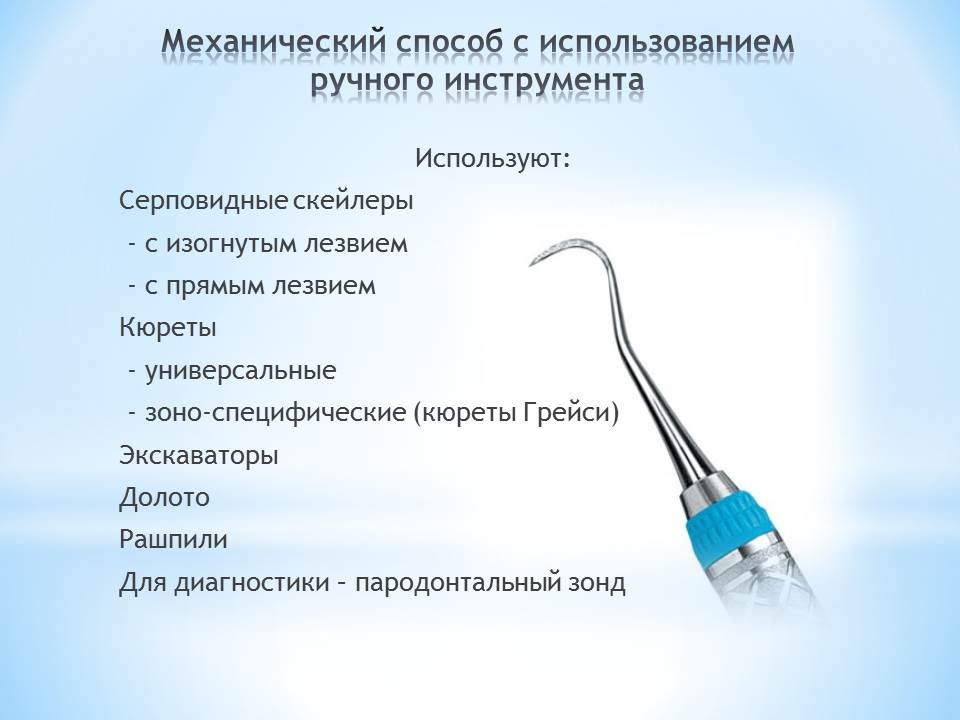

Этапы чистки зубов: Правильный уход за полостью рта

Раздел: Снимки-подсказки